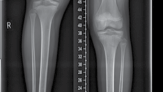

| Figure 15.15 Growth arrest in a 12-year-old child. are held over the magnet within the nail, resulting in rotation of the implant magnet which can either lengthen or shorten the nail with sub-millimeter accuracy. Early results are favourable confirming faster regenerate healing times, less complications, better cosmetic results and more favourable patient outcomes compared to lengthening using an external fixator (Figures 15.14–15.17). | |||

Figure 15.16 Completion of lengthening (8 cm).

6 weeks post lengthening 3 months post lengthening

Figure 15.17 Consolidation (8 cm).